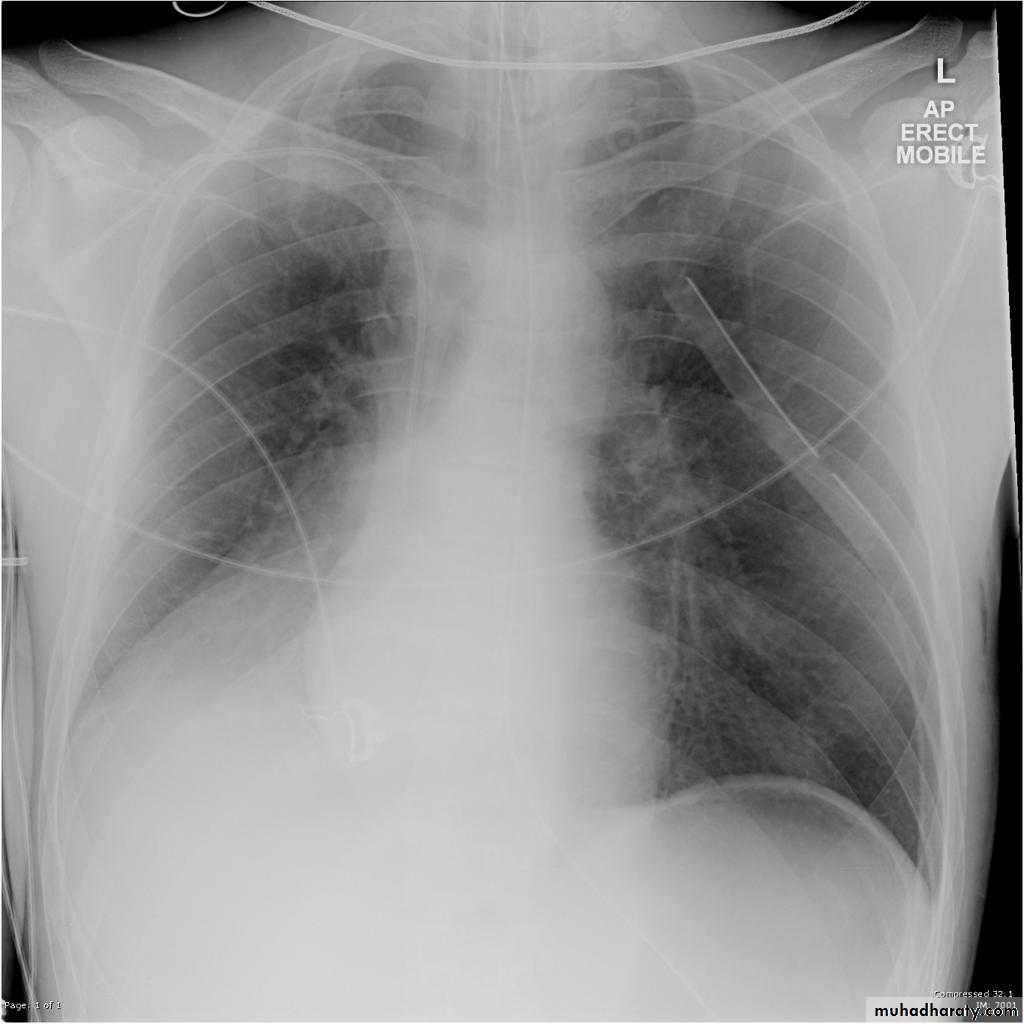

Right middle lobe collapse has distinctive features, and is usually relatively easily identified.

Radiographic features

Chest radiograph

Frontal chest XR showing opasity cause obscuration of the RT cardiac border

Lateral chest XR film the opacity is tongue like shape

versus (triangular in shape) in RT middle lobe consolidation seen in lateral chest XR film